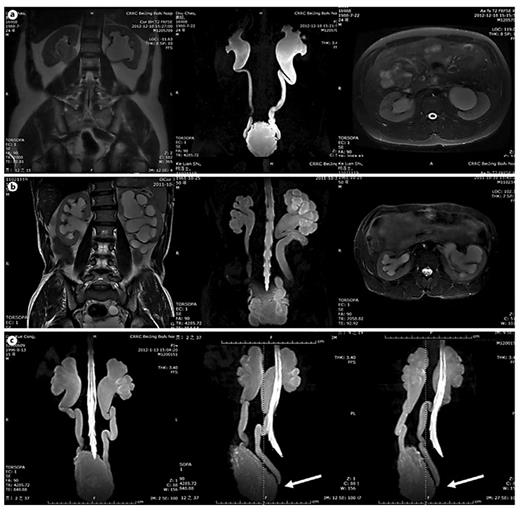

In table 1, LUTD is described according to the Guidelines of the European Association of Urology (EAU) [2] and the terminology of the International Continence Society (ICS) [5]. VUR was graded according to the IRSG, and kidney function was determined by the glomerular filtration rate from isotope renography and the serum level of creatinine. UUTD was graded as follows: grade 0, the central renal complex is closely apposed without UD (fig. 1a); grade 1, slight separation of the central renal complex exists, and the ureter is <7 mm in diameter (fig. 1b); grade 2, the renal pelvis is further dilated, a single or a few calices may be visualized and the ureter is <10 mm in diameter (fig. 1c); grade 3, the renal pelvis is dilated, there are fluid-filled calices throughout the kidney, the renal parenchyma overlying the calices has thinned (renal parenchyma loss <50%), and the ureter is tortuous and <15 mm in diameter (fig. 2a), and grade 4, similar to grade 3, but the renal parenchyma over the calices is thinned (renal parenchyma loss >50%), the ureter is severely tortuous and the ureter is >15 mm in diameter (fig. 2b). For NB patients, detrusor fibrosis and thickening secondary to progressive destruction of the bladder wall often result in ureteral strictures within the bladder wall and distal ureteral obstruction (fig. 2c), which is an important factor in the etiology of UUTD, including HN and UD, and often results in chronic renal failure. Therefore, this new system better discriminates among grade changes in UUT function, can provide objective indicators for UUT function and is an important component of long-term follow-up of conservative and surgical treatment (fig. 3).

MRU UUTD grades 3-4 and distal ureteral obstruction. a Grade 3 UUTD: MRU shows that the renal pelvis is dilated, there are fluid-filled calices throughout the left kidney, the renal parenchyma overlying the calices has thinned (renal parenchyma loss <50%), and the left ureter is tortuous and <15 mm in diameter. b Grade 4 UUTD: MRU shows that the bilateral renal pelvises are seriously dilated, there are fluid-filled calices throughout the kidneys, the renal parenchyma over the calices is thinned (renal parenchyma loss >50%), and the bilateral ureters are severely tortuous and >15 mm in diameter. c Distal ureteral obstruction: HN and UD can be displayed during 360° rotation, and vesicoureteral junction stricture or obstruction can be clearly shown (arrows: left and right ureters).

Improvement of UUTD grades by MRU after 6 months of augmentation enterocystoplasty. a Preoperative UUTD grades of right and left kidneys were 3 and 4, respectively. b Postoperative UUTD grades of right and left kidneys became 0 and 1, respectively. A significant improvement is shown.